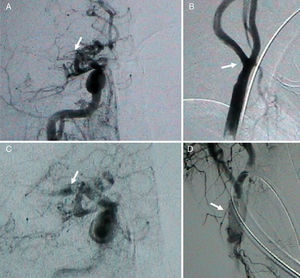

Arteriografía. La imagen A muestra el territorio intracraneal anterior, donde se aprecia una ausencia de flujo en toda la arteria cerebral media derecha (ACMD) y sus ramas (flecha). La imagen B muestra la arteria carótida interna cervical y la bifurcación carotídea derecha con signos de trombo mural (flecha). La imagen C muestra la ACMD tras realizar trombectomía con el dispositivo MERCI. Ahora la porción M1 de la ACMD es visible (flecha). La imagen D muestra el stent colocado en la bifurcación carotídeo derecha (flecha).

Ante la persistencia de la clínica y la presencia de una oclusión de la ACMD se decidió tratamiento endovascular. Como se había sobrepasado la ventana de 6h para el tratamiento con rtPA intraarterial, se planteó una trombectomía mecánica en la ACMD con dispositivo MERCI. Sin embargo, el trombo de gran tamaño en la bifurcación carotídea ipsolateral presentaba el riesgo de fragmentarse nuevamente, con la liberación de émbolos, durante la manipulación del dispositivo MERCI. Tras estudiar el riego-beneficio, se decidió la colocación de un stent a nivel del trombo carotídeo, con previa colocación de filtro de protección distal y heparinización sistémica, con el fin de desplazarlo hacia la pared arterial, eliminar el riesgo de fragmentación y facilitar el acceso a su través hacia el territorio intracraneal. Tras colocar el stent carotídeo, se procede a la extracción parcial del trombo con un solo pase del dispositivo MERCI, obteniendo una recanalización parcial del segmento M1 (fig. 2). No se realizaron nuevos pases con el dispositivo MERCI debido a la reciente colocación del stent carotídeo. Se utilizó doble antiagregación plaquetaria con aspirina 100mg y clopidogrel 75mg.